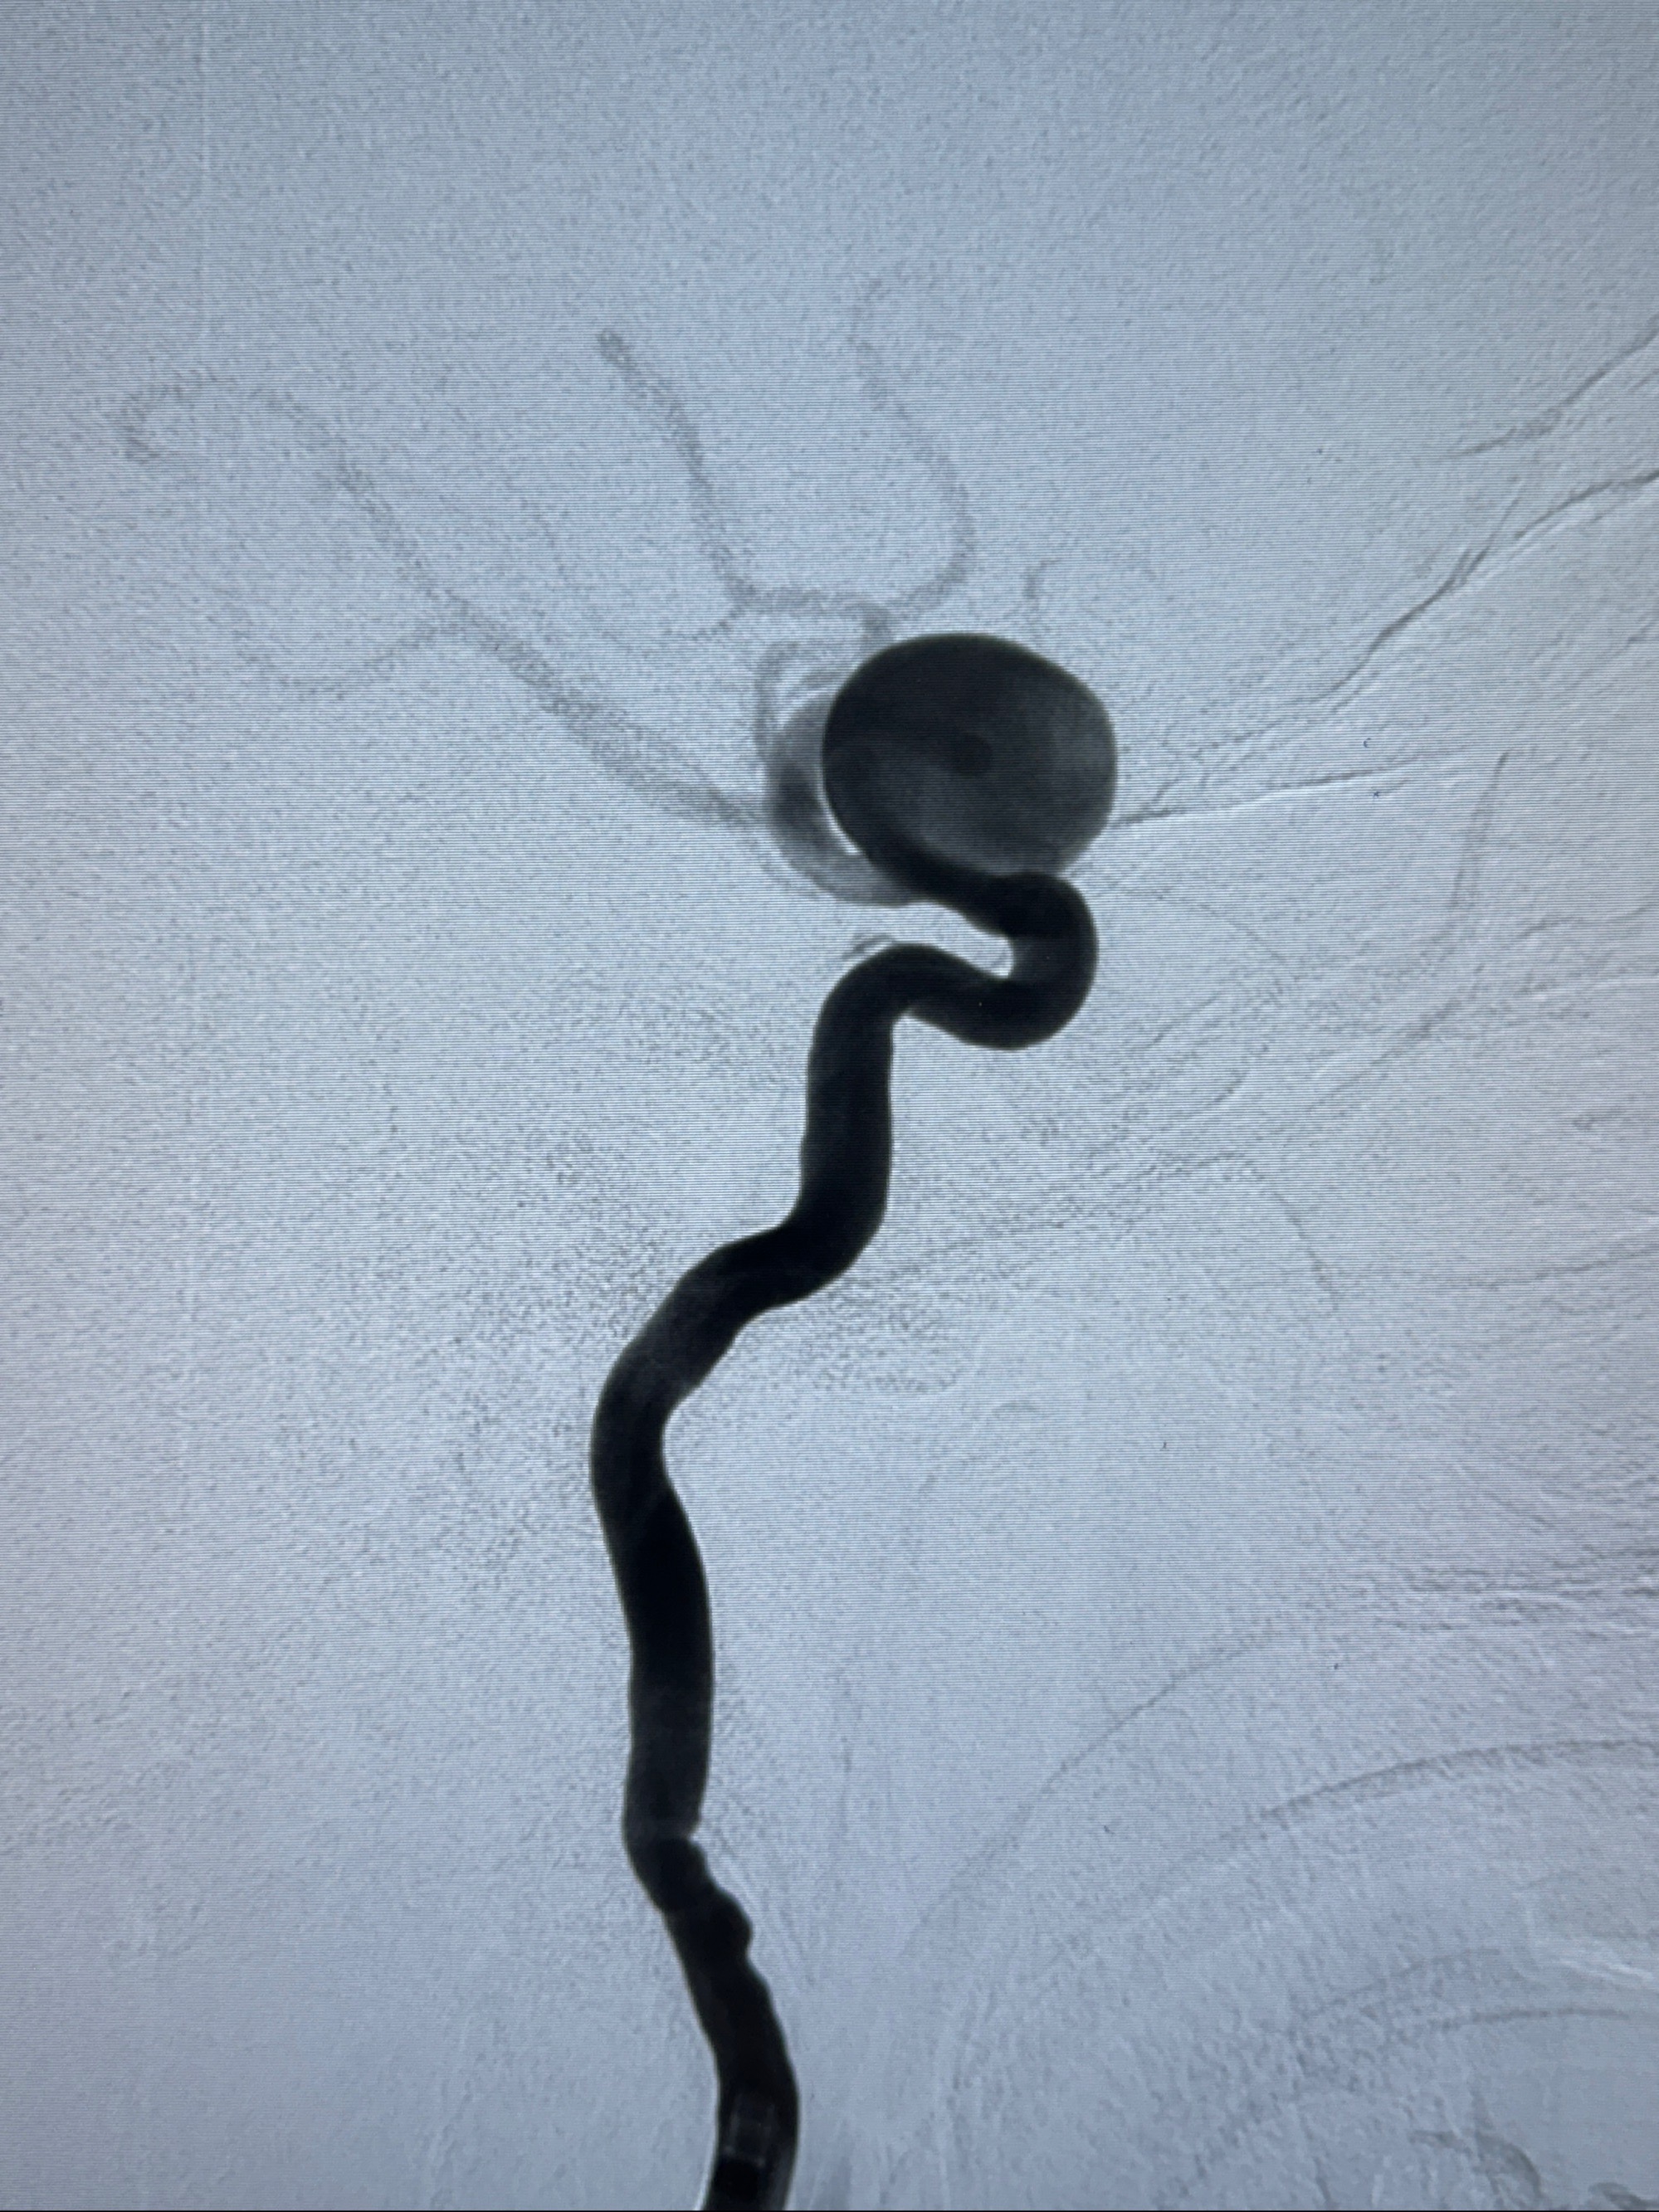

2023-12-27术后第十天复查DSA

支架贴壁佳,但可见射流,咋办?

支架植入顺利,贴壁佳,支架内血流通畅,动脉瘤内血液滞留明显